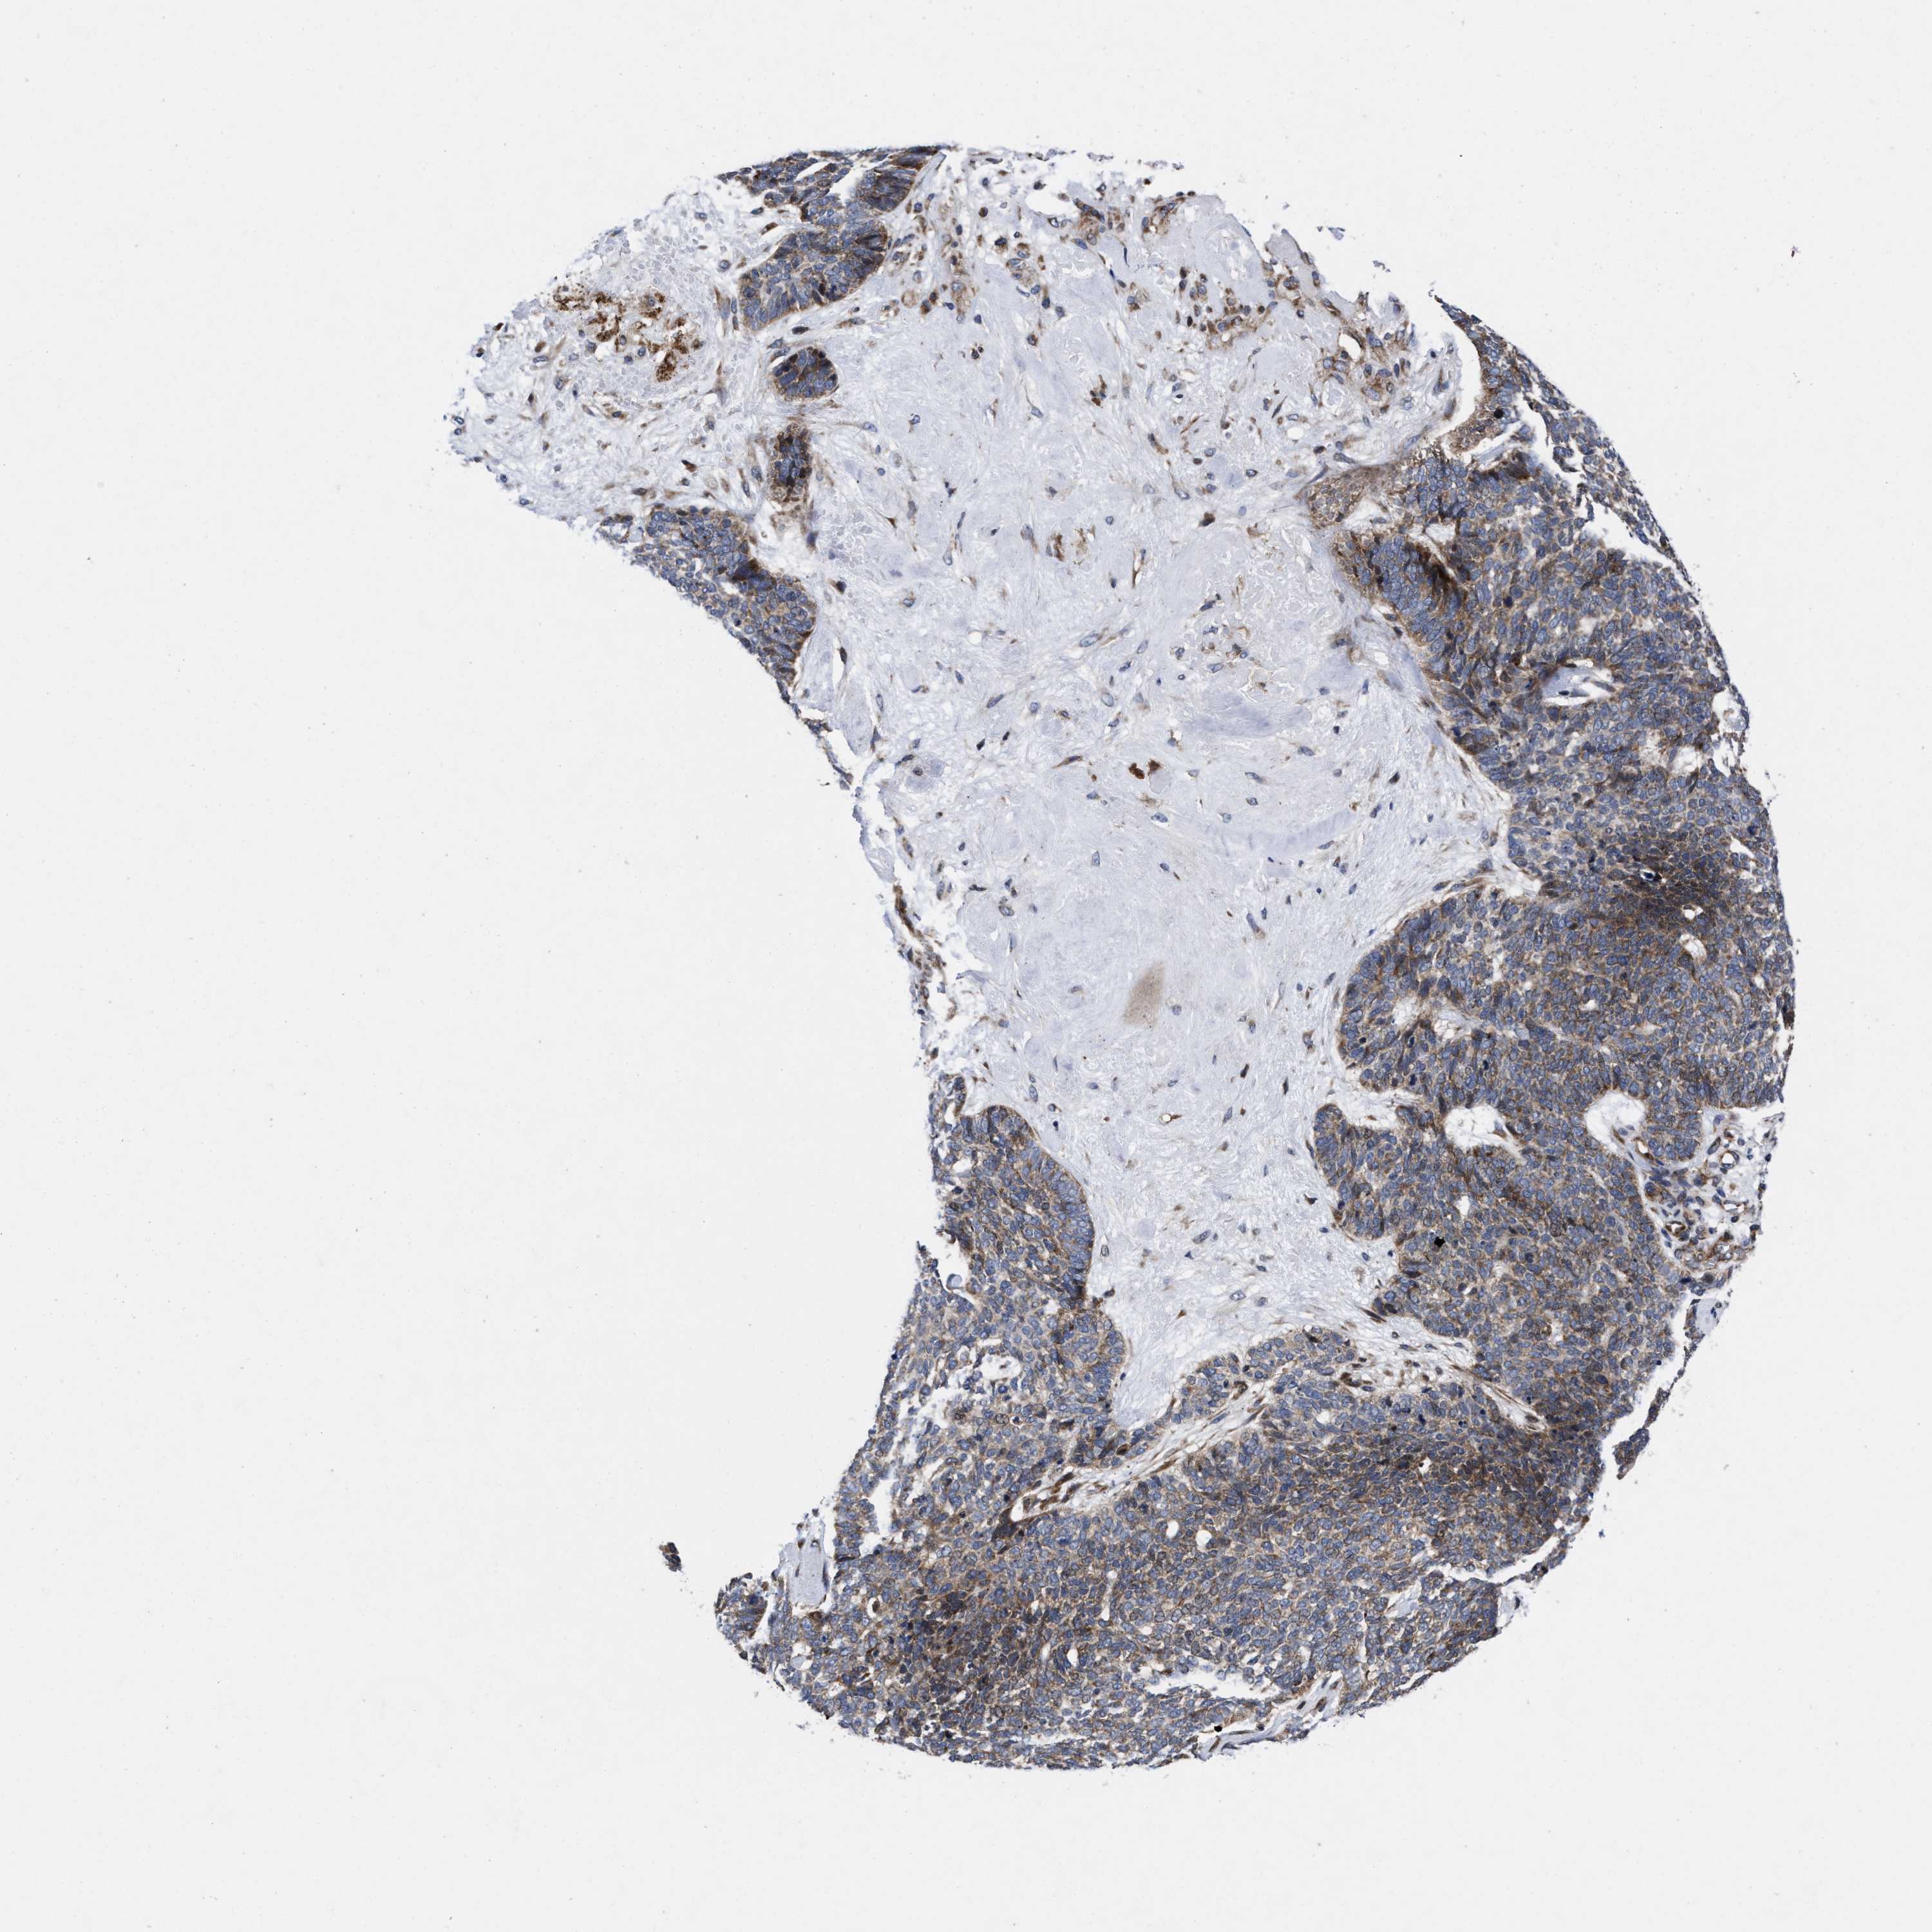

SKIN CANCER - Protein expressioni

A mouse-over function shows sample information and annotation data. Click on an image to view it in a full screen mode. Samples can be filtered based on level of antibody staining by selecting one or several of the following categories: high, medium, low and not detected. The assay and annotation is described here.

Antibody stainingi

Antibody staining in the annotated cell types in the current human tissue is reported as not detected, low, medium, or high, based on conventional immunohistochemistry profiling in selected tissues. This score is based on the combination of the staining intensity and fraction of stained cells.

Each image is clickable and will lead to virtual microscopy that enables deeper exploration of all samples and also displays staining intensity scores, fraction scores and subcellular localization as well as patient and tissue information for each sample.

Antibody HPA022925

Staining

High

Medium

Low

Not detected

Intensity

Strong

Moderate

Weak

Negative

Quantity

>75%

75%-25%

<25%

None

Location

Nuclear

Cytoplasmic/membranous

Cytoplasmic/membranous,nuclear

Squamous cell carcinoma, NOS

Basal cell carcinoma

Adnexal tumor, benign